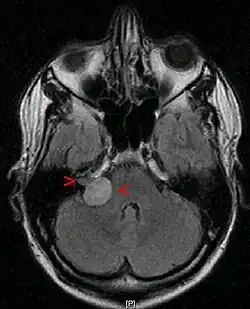

Neuroma do acústico, visto através de um exame de ressonância magnética

A ressonância magnética é a imagem de escolha, porque pode diferenciar com mais precisão a massa de outros tumores, como meningioma , schwannoma do nervo facial, cisto epidermóide, cisto aracnóide, aneurisma e metástase cerebral. A ressonância magnética também ajuda no planejamento cirúrgico e no acompanhamento do tumor após a cirurgia.[7]